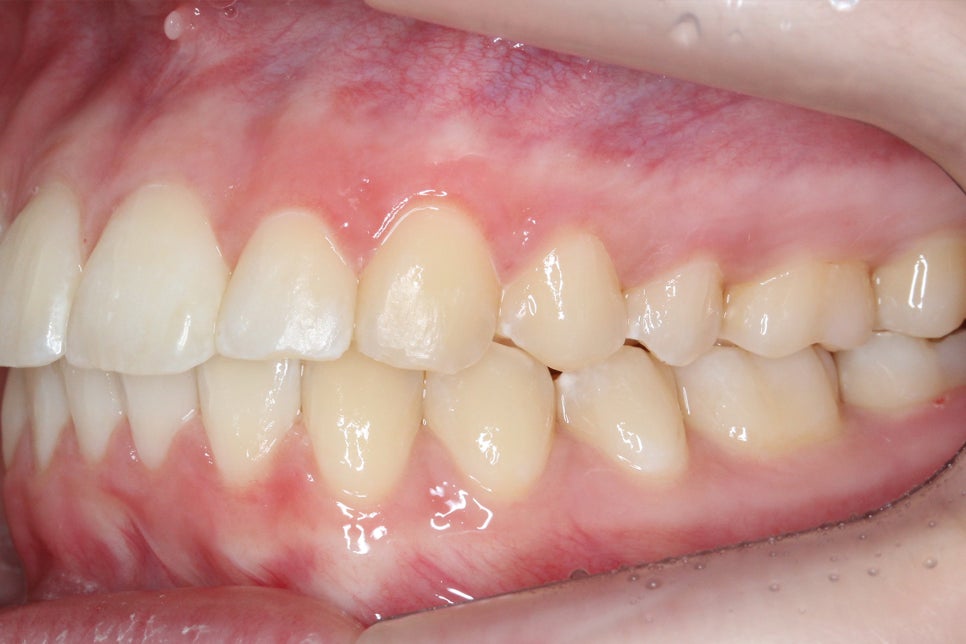

아랫니의 경우 전치부의 총생이 심하고

삐뚤어진 부분에 치석과 치태가

쌓일 위험이 있기 때문에

바른 치아 배열을 중점적으로

비발치 클리피씨교정을 진행하였습니다.

투디치과 환자분의 교정 후 아랫니의 모습을 보면

총생이 심했던 전치부 치열이 몰라볼 정도로

가지런해진 것을 확인할 수 있는데요,

삐뚤거리던 치아가 바르게 배열되면서

치석과 치태가 사라진 모습입니다.

전체적인 안모의 형태도 이상적인

곡선을 그리는 모습으로 비발치로 진행하였지만

비교적 단기간에 교정을 마무리할 수 있었는데요,